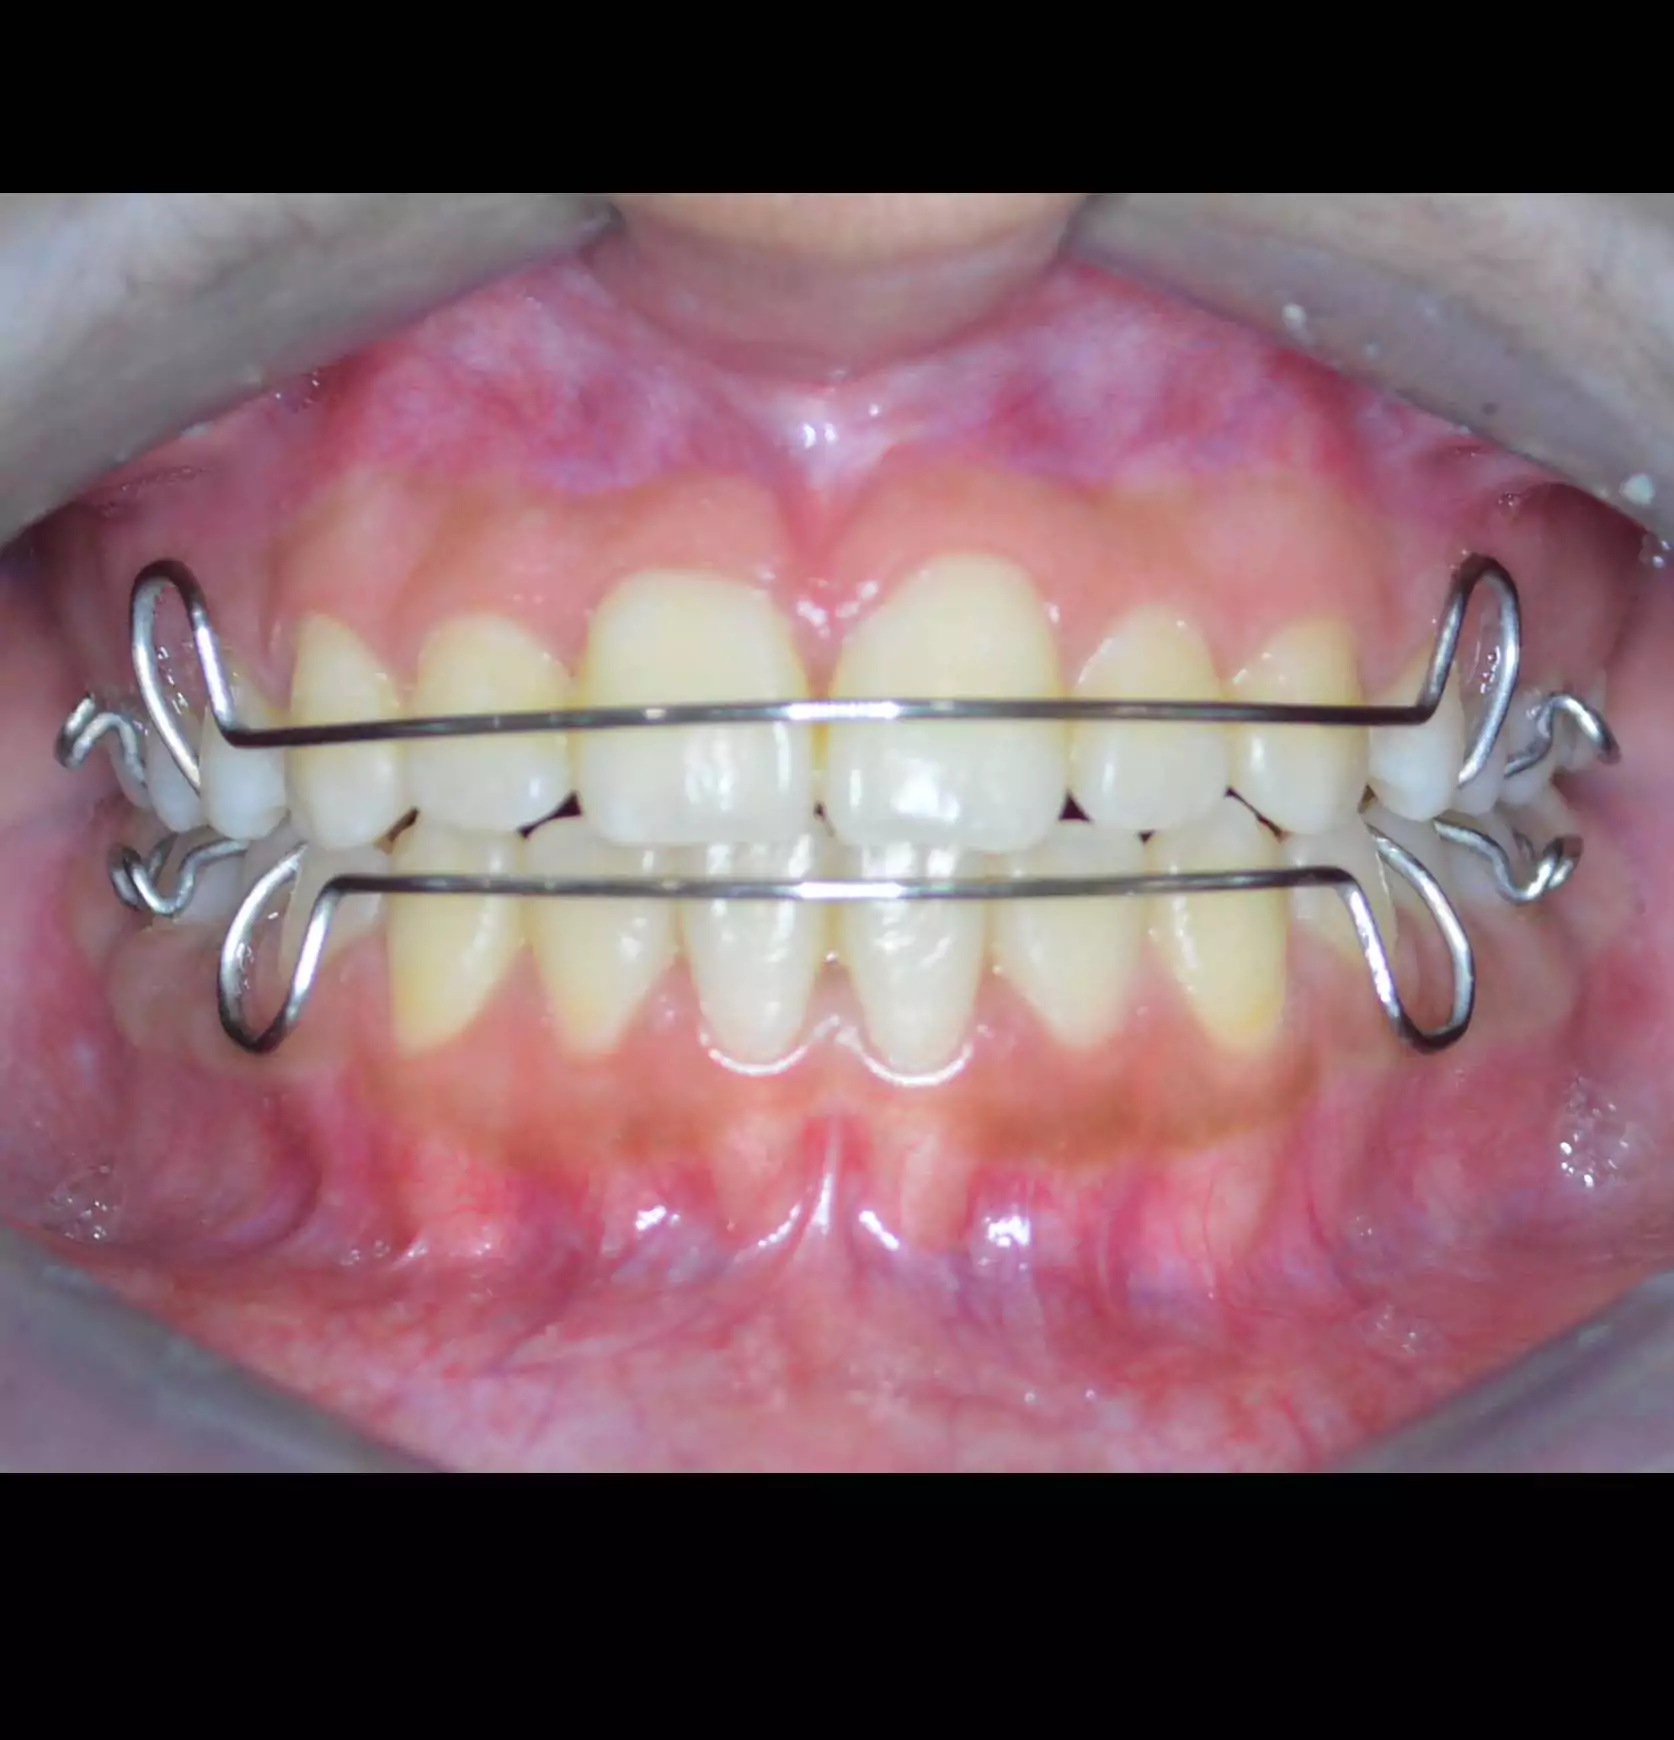

Orthodontic Case – II

(Case Done by Dr. Sonali Deshmukh M.D.S. / Orthodontist )

Correction Of Protruded

Small Lower Jaw

A child with protruded teeth and a small lower jaw at a young age can be treated by Myofunctional appliances which help in the growth of the jaw.

Pre Treatment

After Myofunctional appliances therapy for jaw growth accompanied by braces treatment for correction of protruded teeth.